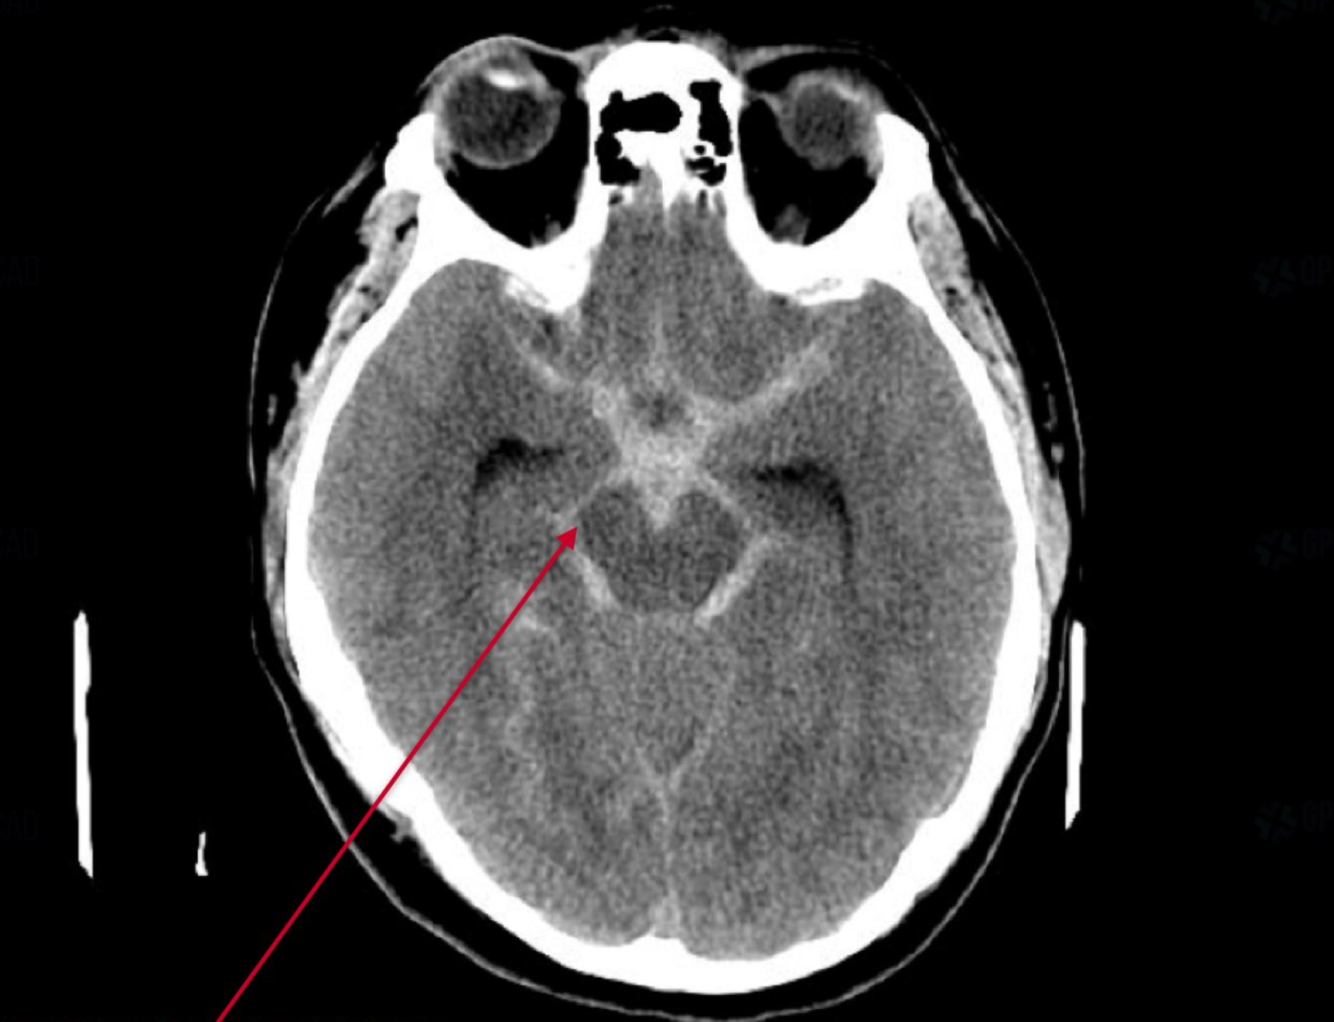

subarachnoid haemorrhage